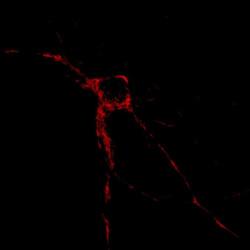

Los científicos descubren cómo los humanos desarrollan cerebros más grandes que otros simios

Un nuevo estudio es el primero en identificar cómo los cerebros humanos crecen mucho más, con tres veces más neuronas, en comparación con los cerebros de chimpancés y gorilas. El estudio, dirigido por investigadores del Laboratorio de Biología Molecular del Consejo de Investigación Médica (MRC), en Cambridge (Reino Unido), identificó un interruptor molecular clave que puede hacer que los organoides cerebrales de los simios crezcan más como los humanos, y viceversa.